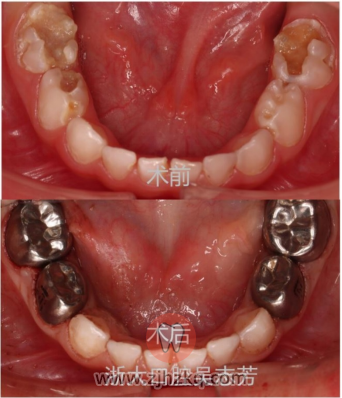

儿童牙套也有三种不同材质:不锈钢金属预成冠(小钢牙)、树脂透明冠和全瓷预成冠。

不锈钢金属预成冠材质为不锈钢,硬度高,颜色为银灰色,美观度欠缺,比较适合用于后牙而非前牙。需要注意的是,金属预成冠不适用于对不锈钢材料过敏或者需要做头部核磁共振的儿童。